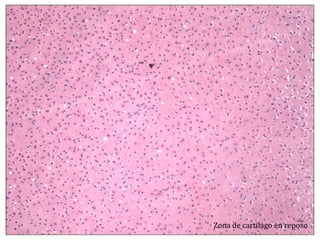

El documento describe diferentes aspectos de la histología del cartílago y el hueso, incluyendo las estructuras del cartílago como condroblastos, matriz y lagunas, y las estructuras óseas como conductos de Havers, osteoblastos y osteoclastos. También describe las etapas de la osificación endocondral, el proceso por el cual el cartílago se transforma en hueso, incluyendo las zonas de cartílago en reposo, proliferación, hipertrofia, erosión y osificación.